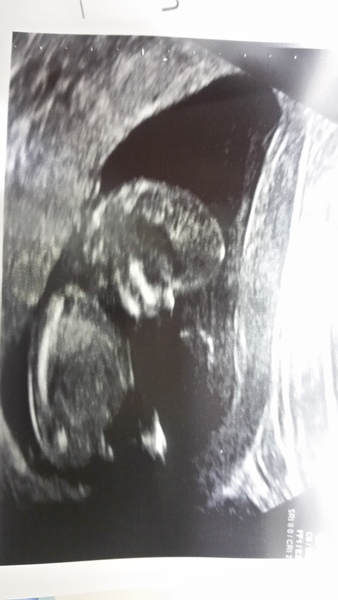

Lovely scan lingo. I was put back a day on my scan too. It's amazing how different they still can look though as there is only 4 days between us. I'll attach a pic of my little (big!) jalapeño now.

Ghostonthedancefloor · 31/10/2016 20:42

Here's my naughty one! It was so cute though. He/she just would not get their hand away from their face, and at one point was playing with the nose! It's so so amazing. What our bodies can create in a matter of weeks.